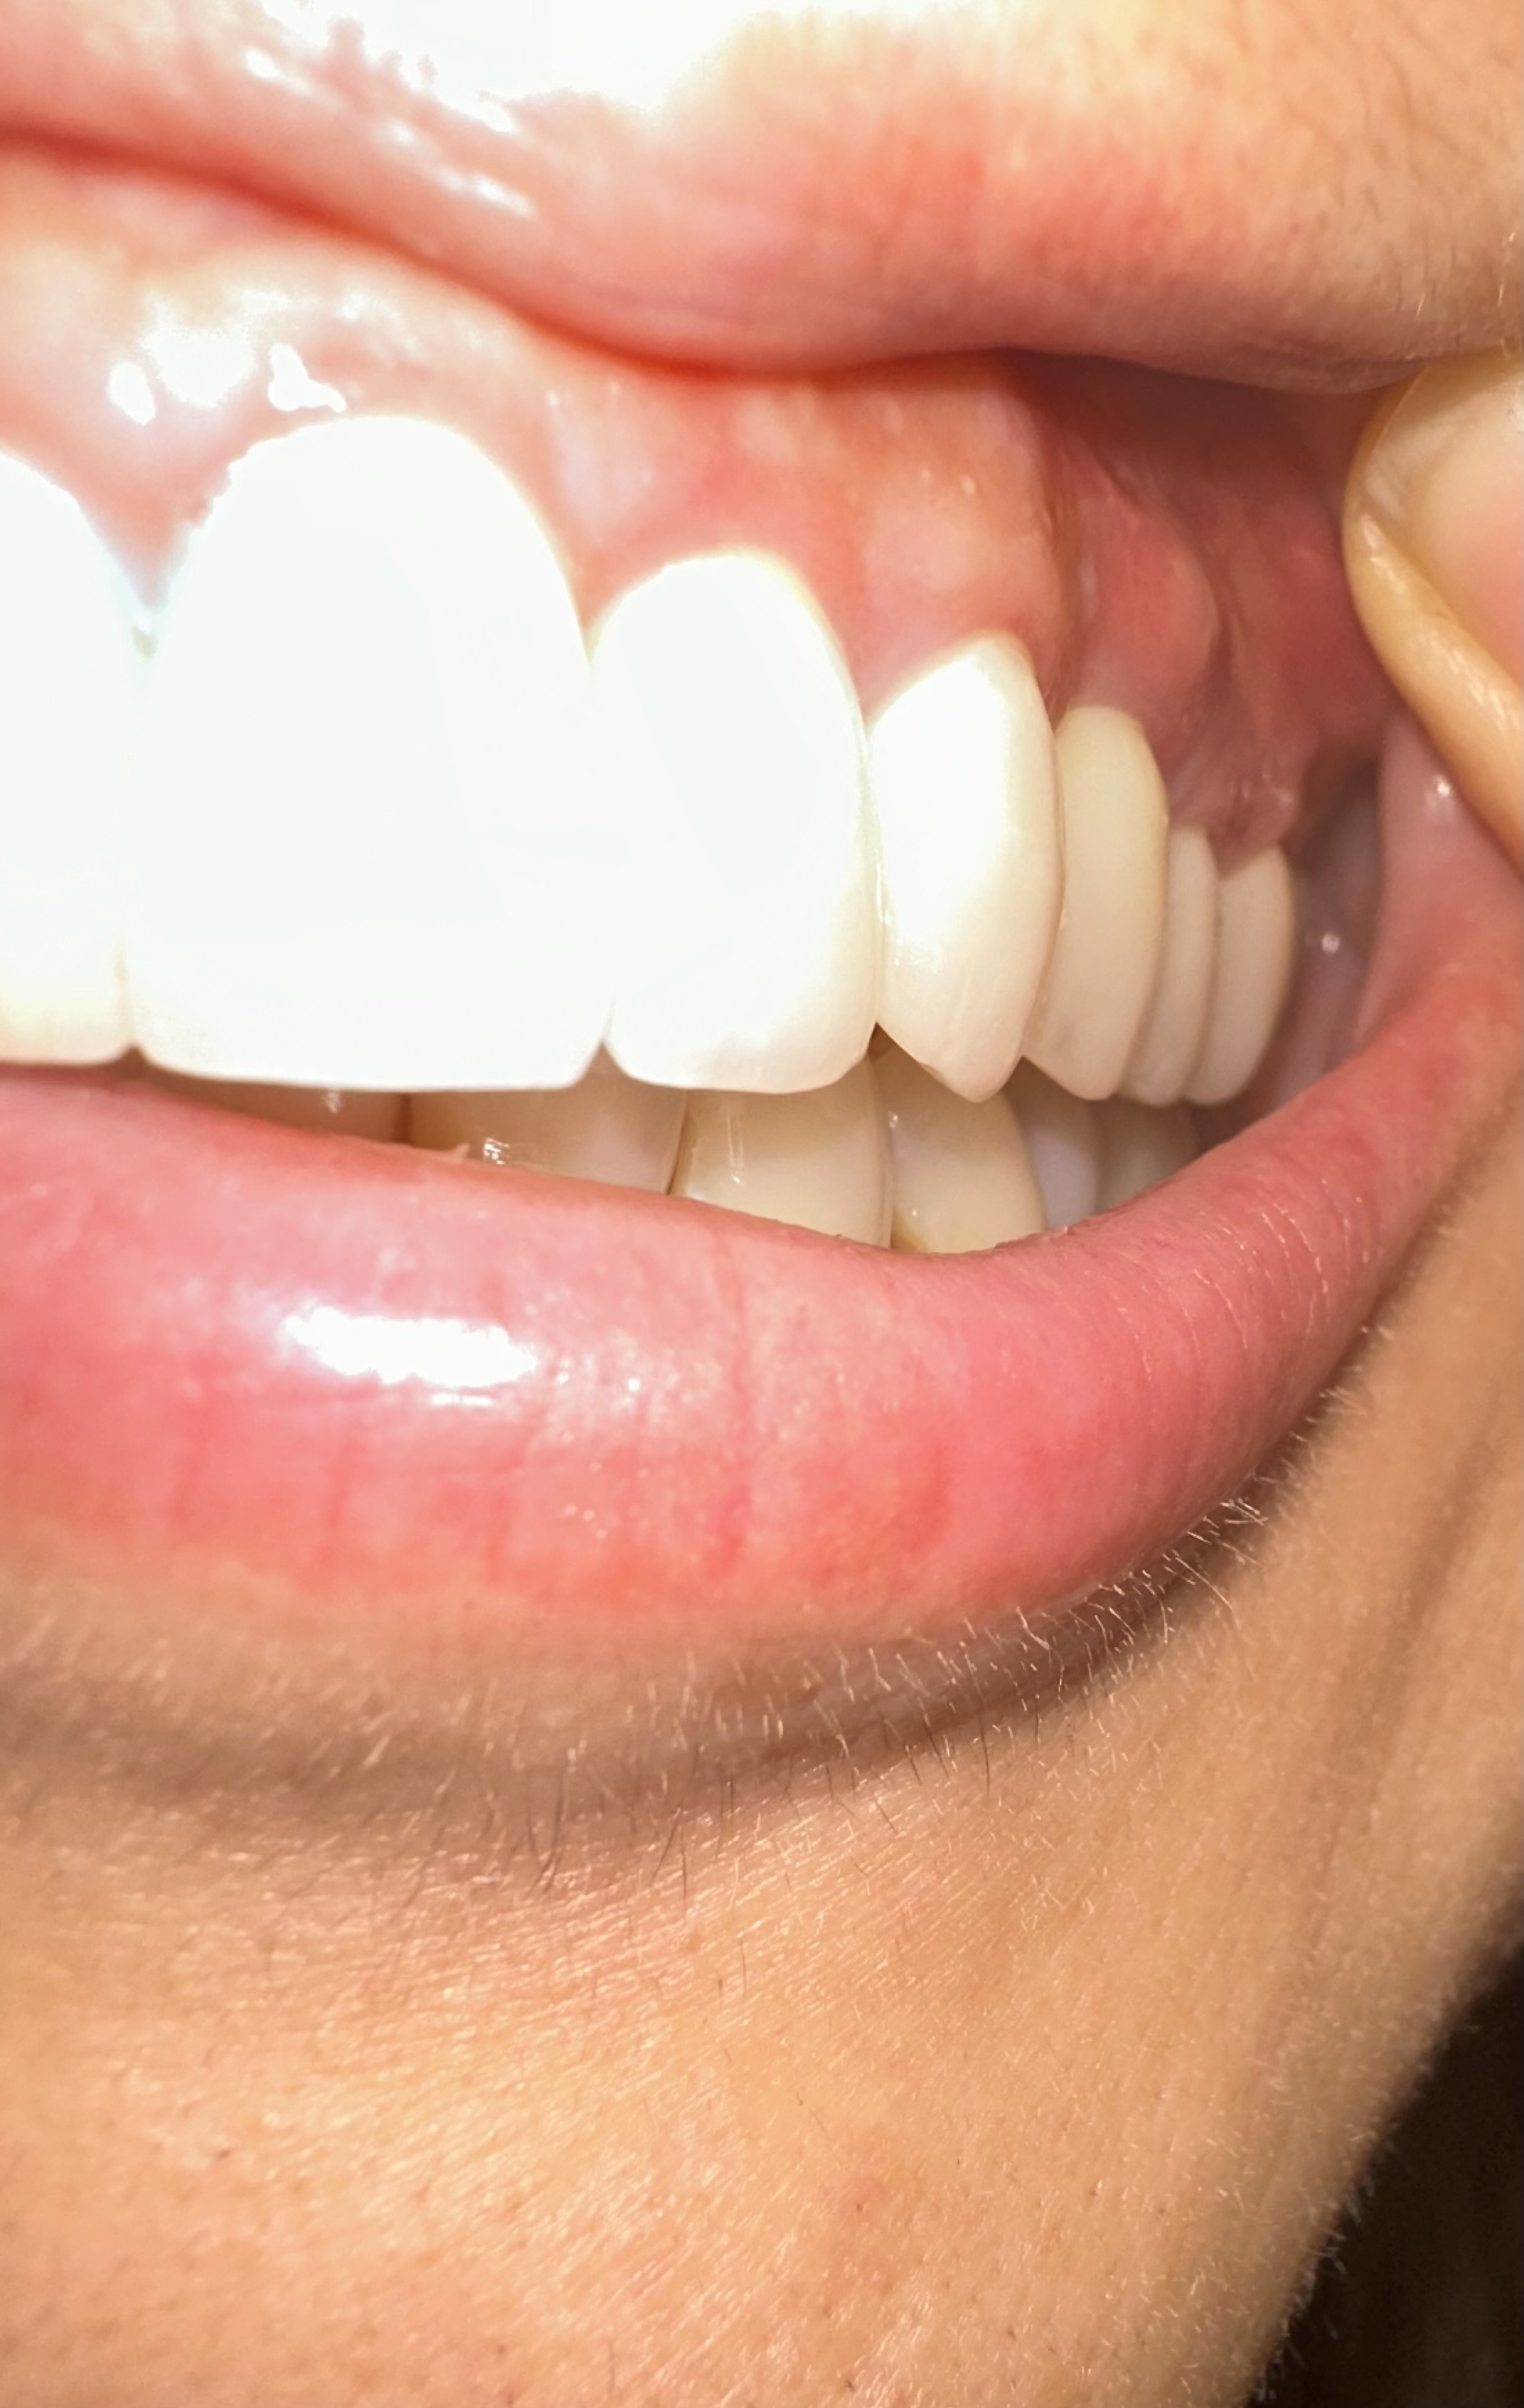

フィステルのようなものができているのは、調べたところ「第一小臼歯」の上でした。

先生のお話では、このできものはフィステルであるとのことで、原因としては側切歯の根の部分に炎症があるのでそこの歯からの可能性が高いそうです。

今回のフィステルが二つ隣の歯にできるということは本当にあるのでしょうか?